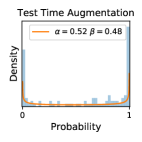

5.1 Distribution of Uncertainty Scores

Comparing the three ensemble methods in Figure 4, the stacking ensemble method has the highest ratios of SL1 & SL2 data among the high-uncertainty examples it identified under both mean and var. TTA showed slightly better performance than MC-dropout but still falls behind the stacking ensemble method. Considering the fact that SL0 examples accounted for the majority of the dataset, the stacking ensemble method was much more precise (specific) in selecting truly ambiguous data points that were difficult to classify. From Figure 3, we can also see that the stacking ensemble method greatly outperformed the other two methods in finding false negatives under both mean and var uncertainty metrics.

In contrast, the MC-dropout method showed the worst overall performance among the three, as it can be seen from the high ratios of SL0 examples among the uncertain negatives in Figure 4. The histograms in Figure 2 provides another perspective to look into the phenomenon, where a decent proportion of MC-dropout model’s predictions on SL0 inputs entailed low confidence (far from 0 or 1), which from another angle explained why MC-dropout was less specific in terms of lower FNP; many no-DR inputs (i.e. SL0) were erroneously assigned high uncertainty by MC-dropout models.

It is still an open question why the evaluated MC-dropout networks signaled relatively high uncertainty on SL0 & SL3 & SL4 data that are less likely to be ambiguous. We conjecture that much of the “uncertainty” indicated by disagreement among test-time dropout samples actually reflects the stochastic nature of dropout networks rather than the real decision uncertainty associated with the data. It is worth noting that the MC-dropout model we evaluated was not weak per se; they all achieved above Area Under Curve (AUC) scores on test sets. The weakness of individual test-time samples (which explains their low-confidence predictions on SL0 & SL3 & SL4) might have been hidden when they are aggregated into an ensemble—a well-known advantage of ensemble learning. Our results suggested that the uncertainty information given by implicit ensemble methods such as MC-dropout and TTA might not be as reliable as that from explicit ensemble approaches (e.g., stacking ensembles). Similar findings on MC-dropout can be found in some previous papers [1].